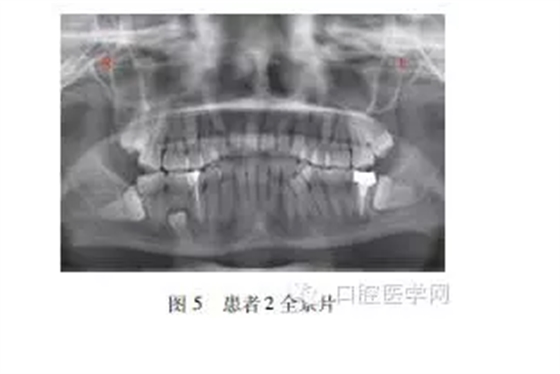

患者2,女,23歲,無遺傳史,母親孕期無特殊接觸史。??茩z查:恒牙28顆,牙列擁擠,4舌側(cè)可見1顆多生牙,形態(tài)大小似前磨牙,57可見充填物。全景片(圖5)示患者88垂直阻生,88近中阻生,45間可見一多生牙近中傾斜萌出,55根方可見一埋伏阻生多生牙,6根方可見一含牙囊腫,內(nèi)含埋伏阻生多生牙牙冠。

治療計(jì)劃:分次拔除下頜2顆多生牙,上頜2顆多生牙因無臨床癥狀,可暫觀察。

多生牙發(fā)病一般認(rèn)為與遺傳和環(huán)境因素有關(guān),本資料中2例患者的多顆多生牙形態(tài)均與同位牙類似,應(yīng)該均由一個(gè)牙胚分裂多生而來,且均為成對(duì)多生。第1例存在9顆多生牙,而正常牙齒32顆萌出完全,排列整齊,實(shí)屬罕見,該病例有家族史,與遺傳密切相關(guān)。第2例存在4顆多生牙,牙列擁擠,無家族史,右下頜埋伏多生牙誘發(fā)牙源性囊腫,需盡早拔除。